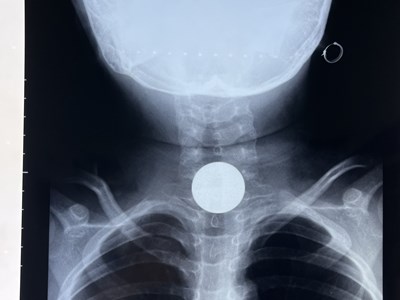

Sáng 22.2, bé trai 11 tuổi, ở xã Tịnh Châu, TP Quảng Ngãi, được người nhà đưa vào Bệnh viện Sản - Nhi tỉnh Quảng Ngãi trong tình trạng nghẹn, đau tức vùng ngực. Qua thăm khám lâm sàng, chụp Xquang, siêu âm vùng ngực, bụng bác sĩ xác định có dị vật trong đường tiêu hóa.

Ngay sau đó, bệnh nhi được chuyển đến Khoa gây mê hồi sức để thực hiện thủ thuật gắp dị vật. Tại đây, các bác sĩ đã gắp ra nắp của lon nước ngọt bằng nhôm trong dạ dày, có kích thước 2cm.